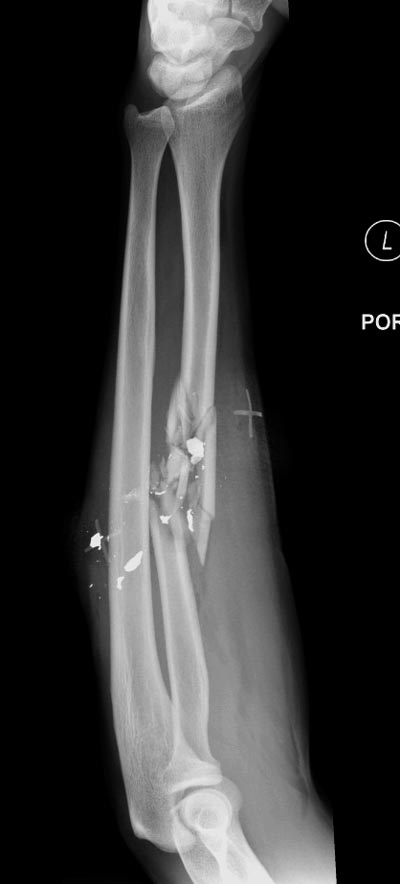

Здесь примеры: двоюродные братья с ранением предплечья, у одного локтевая, а у второго лучевая. В следующее утро локтевая фиксирована без обнажения фокуса травмы из небольших доступов, а второй из обычного волярного доступа. А клинический снимок из прошлых операций...